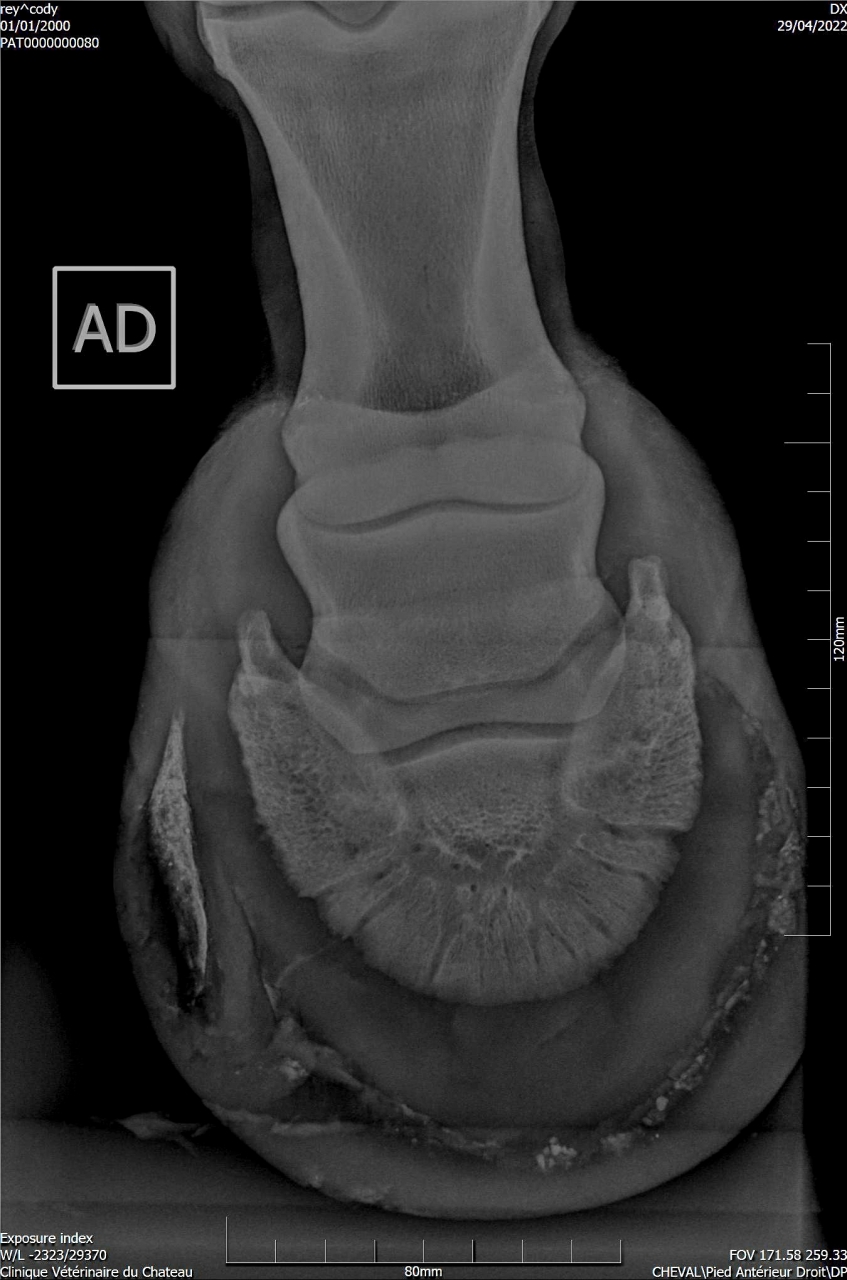

| Dire merci | Suite aux radios faites sur Cody, j'ai fait passer un véto spécialisé en boiteries. Examen : AG paturon légèrement déformé (je n’avais jamais remarqué) Pince + Fers avec oignons et plaques Planche négative (apparemment Cody a bien réagi) Flexions statiques normales Légère irrégularité ADT à main dte (effectivement pas trop mal, ça a été pire) Radiographies fournies : Légère ossification processus palmaires (moi je ne vois rien de particulier sur les radios) Légère arthrose interphalangienne proximale (idem) 1 à 3 fossettes sur chaque naviculaire (apparemment pas catastrophique, le véto m’a montré d’autres radios de chevaux naviculaires pour comparer) Recommandations : Marechalerie : poursuivre à l’identique (Oignons et plaques) Traitement : Dextropine et Navitol Voici les radios : ![]() ![]() ![]() ![]() Si quelqu'un pouvait m’expliquer en termes simples ![]() |

| Dire merci | Je suis pas experte en lecture de radios, loin de là, mais le bord distal du naviculaire semble quand même largement plus vilain que les cartilages palmaires ? Et ça sur les deux pieds.Je serai par contre curieuse de voir des photos du parage vu ce qu’on voit aux radios.. Message édité le 01/07/22 à 22:45 |

| Dire merci | La où il y a les fossettes. En gros la partie en rapport avec le tendon du fléchisseur profond. Mais il a l’air d’être super long au moment des radios? |

| Dire merci | Honnêtement j'ai vu bien pire en ossification des processus palmaires, il faut que je retrouve les radios. Pour le reste je rejoins les autres les pieds sont beaucoup beaucoup trop longs. |

| Dire merci | Je pense qu’un cheval sur deux aura les cartilages plus calcifiés que celui là Peut être même plus… Son plus gros soucis sur les radios c’est quand même l’entretien des pieds. Et c’est le seul facteur sur lequel on peut jouer et qui n’est pas irréversible Faire un parage coûte moins cher que 2 paires de radios |